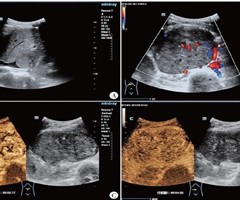

下腔静脉平滑肌肉瘤超声表现1例

[中图法分类号]R445.1;R543.6 [文献标识码]B 患者女,26岁,因“扪及右下腹包块 4+ 个月”入院。体格检查:腹部略膨隆。实验室检查:糖类抗原 19-949.40U/ml ,乙肝表面抗体定量 22.8U/L ,降钙素原 0....